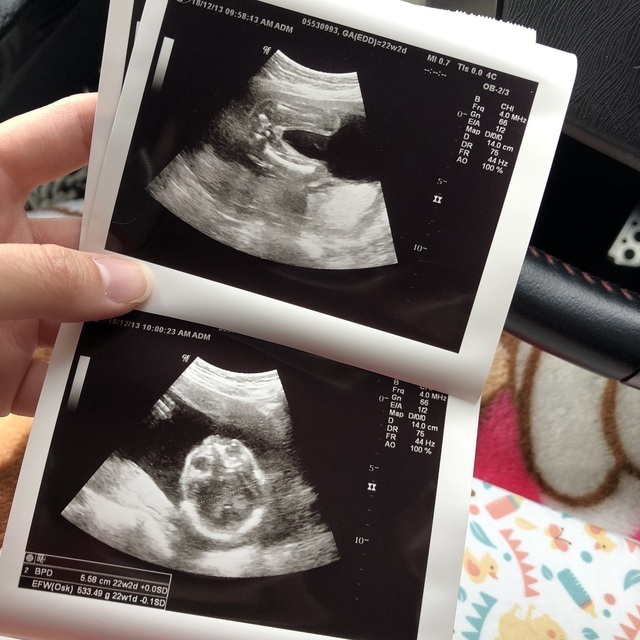

22週2日(22w2d・男の子)|きょろ さん(24歳)

エコー写真撮影時のエピソード:

初めての4Dエコー!残念ながら左手で顔を隠していて全体がみえず…次の時に期待してます。 しかし、次の最後の4Dエコーでしたが、それも顔を隠してました。

必ずやどちらかの目を隠していてどんな顔か、片方ずつで全体がわからなかったので産まれるまでがまた楽しみになりました。

体調は良好でエコーを見る度にドキドキ。 エコーの写真は段々入りきらなくなりわからない程だったなぁて思ってました♡ 初の4Dエコーの写真は記念になりました♡